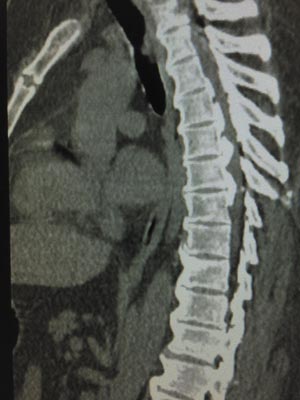

Figure 1: People with the spinal disorder ossification of the posterior longitudinal ligament (OPLL) of the spine have aberrant bone growth in the spine. © Spondylolithesis/ iStock/ Getty Images Plus

Ossification of the posterior longitudinal ligament (OPLL) of the spine is a degenerative disease that afflicts more than 2 per cent of people in Japan. It results when bone starts developing in the soft tissue of the spinal cord, leading to nerve compression, pain and numbness—debilitating symptoms that can affect daily life.